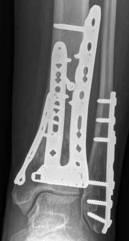

Removal of implants is not mandatory but recommended if implants are prominent under the subcutaneous envelope of the distal tibia. Implant removal should be undertaken only after healing is complete, ie, after 1 year at the earliest. This patient had achieved good radiographic and functional healing at the 1-year postoperative review (Fig 2.2-8 and Fig 2.2-9).

Fig 2.2-8a–b Postoperative x-rays at 1 year showing healed fractures, implants in situ, and limited tibiotalar arthrosis.

1. AP view.

2. Lateral view.